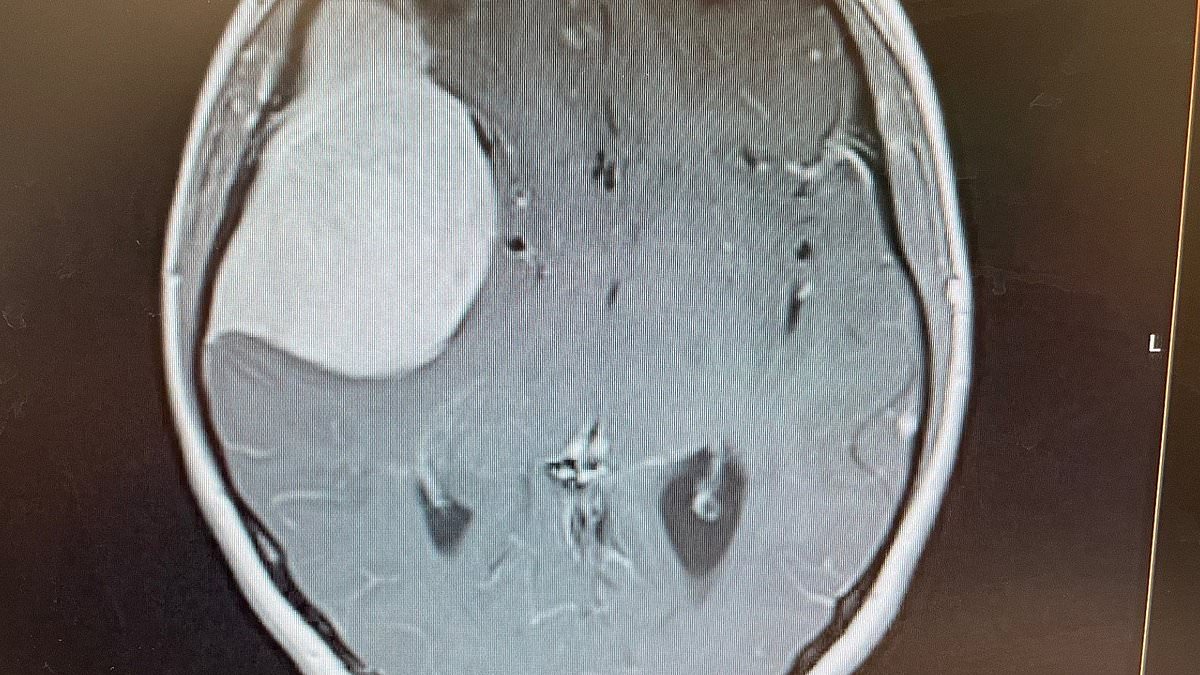

A one-time gene therapy delivered via MRI-guided brain surgery shows substantial slowing of disease in 29 patients, offering new hope for the inherited disorder.

Worswick’s case highlights delays in recognizing brain tumours and fuels calls for greater awareness and new diagnostic safeguards.